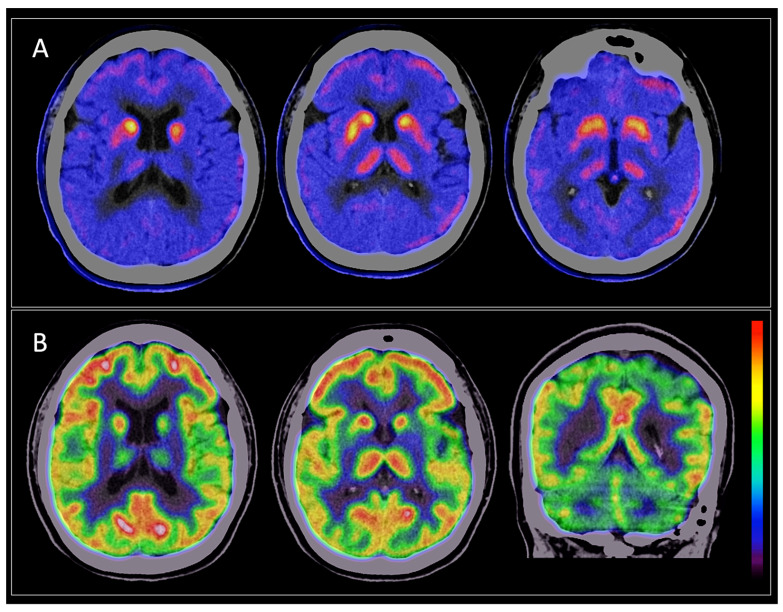

Among the 150 patients, 149 (99.3%) exhibited abnormal findings on FDOPA PET/CT. The most common abnormality observed was a reduction in uptake in the posterior third of the putamen nuclei, which occurred in 89.9% of cases. Only one patient had normal FDOPA PET results, with both clinical diagnosis and dual PET/CT suggesting DLB. An asymmetrical uptake pattern was the most common, seen in 65.1% (n = 97) of cases. Among the different Parkinsonisms, MSA-C was the only diagnosis that displayed both symmetrical and asymmetrical patterns. The asymmetrical pattern was most common in MSA-P (Scheme 1).

3.3. Brain [18F] FDG PET/CT Findings

3.4. Dual FDOPA–FDG PET/CT Diagnosis

Regarding FDG PET/CT findings, 52.67% of patients showed preserved metabolism, which can be explained by the fact that most patients had a clinical and dual PET/CT diagnosis of PD, in whom cerebral glucose metabolism is generally preserved. Metabolic patterns with FDG have been useful in the differential diagnosis of PD, as well as in atypical Parkinsonisms [ref. 29,ref. 30]. These findings correspond with those described by Garraux et al., who concluded that FDG PET/CT accurately distinguishes between PD and atypical Parkinsonisms, a relevant factor for prognosis and treatment [ref. 31]. Figure 1 summarizes the findings from dual FDOPA and FDG PET/CT in our population; until now, this had not been characterized in Mexico, and the results were similar to published data.